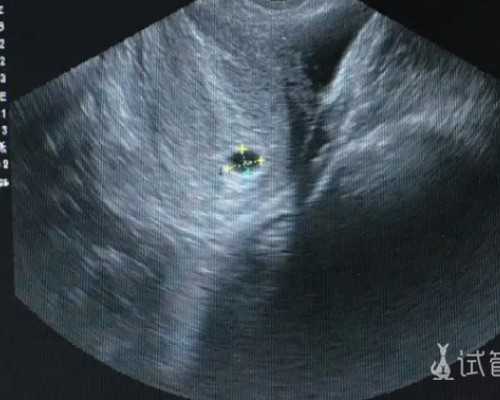

试管婴儿如何选择排卵计划?对于寻求助孕的家庭,这同样关键。越多越好?目前使用的药物大多是进口药物,纯度高,不含任何杂质,采用细针皮下注射,痛苦小,不易引起过敏和出血。对于希望通过代生或代怀实现生育梦想的夫妇,排卵方案的选择尤为重要。很多患者甚至可以在家自行注射,非常方便,也不会影响工作。例如,如果考虑代怀儿子或代生龙凤胎,精细的促排卵管理是成功的第一步。这种用于代孕供卵的促排卵针,就像生病时打针一样,不是什么大手术,所以不必紧张。甚至在一些公立医院代生项目中,患者也能得到专业的指导。